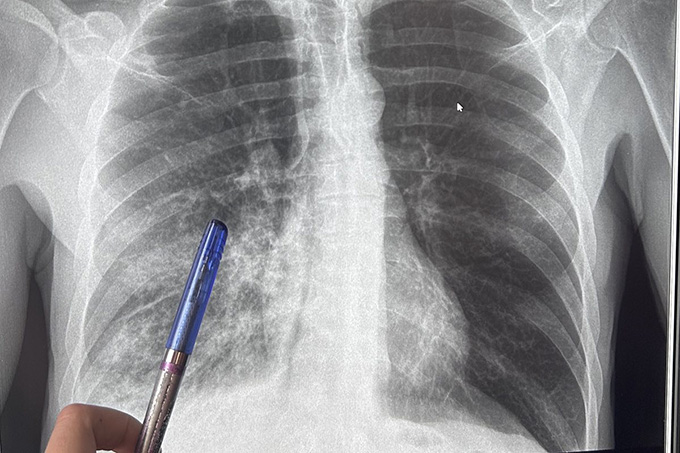

Пневмония, или воспаление лёгких, — одно из самых распространённых инфекционных заболеваний. Согласно статистике от пневмонии ежегодно в мире умирает более двух миллионов человек, в том числе примерно 1,1 миллиона — детей.

Как отмечают медики, к сожалению, пневмония не всегда диагностируется своевременно. Врачи констатируют, что появляется всё больше случаев нетипичного развития болезни. Если раньше пневмонию связывали с холодным временем года, то теперь и в тёплое время года нет гарантии уберечься от неё.

Лечение назначает только врач. При этом учитываются клинические проявления, результаты обследования, тяжесть заболевания. Также во внимание принимается наличие сопутствующих заболеваний, переносимость лекарственных препаратов.